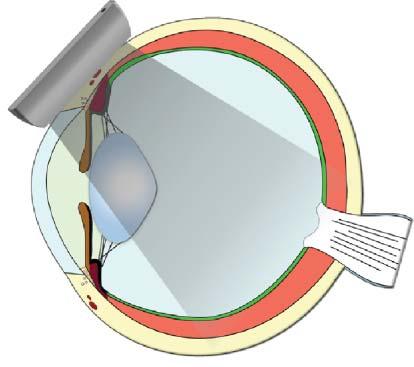

Toproducean image,thefirstpiezoelectriccrystals arestimulatedtogenerateashortultrasoundpulse–comprisingthreetofourwaves–thattravelsthrough tissueinterfacestoproducethousandsofechoes thataresentbacktotheprobe(Figure1.1).Shortly

afterward,anewultrasoundpulseleavestheprobe atadifferentangle,generatinganewsetofechoes thatreturntothesecondseriesofcrystals.Assuminga constantwavepropagationspeedof1,540m/sinsoft tissues,eachoftheseechoescanbelocatedprecisely alongthetrajectory,dependingonthetimeinterval betweenthedepartingwaveandthereturningecho (Hangiandreouetal.2003).Hundredsofwavelinesare producedthisway,scanningtissuesathighspeedto produceover30images/s,eachonecontainingthousandsofpixelsdescribingtheacousticcharacteristics ofthescannedtissues.

Figure1.1. Ultrasoundpropagationandimageformation. Eachultrasoundimageisformedbytheadditionofhundredsofindividualscanlines.Eachlineisproducedaftera singleultrasoundpulse(inyellow)isemittedbythetransducer.Asthispulsepropagatesthroughsofttissues,many echoes(ingreen)aregeneratedatinterfacesofdifferentacousticimpedance(suchashepatocytes–connectivetissue),producinganimageofvariableechogenicityandechotexture. Eachechoisanatomicallylocalizedbasedonthetimeinterval betweentheemittedpulseanditsreception.Afteraspecific time,anewpulseisemittedalonganadjacentline,producing anadditionalscanline.Scanlinesaregeneratedveryrapidly andsuccessively,producing15–60images/s,allowing“real time”ultrasonography.